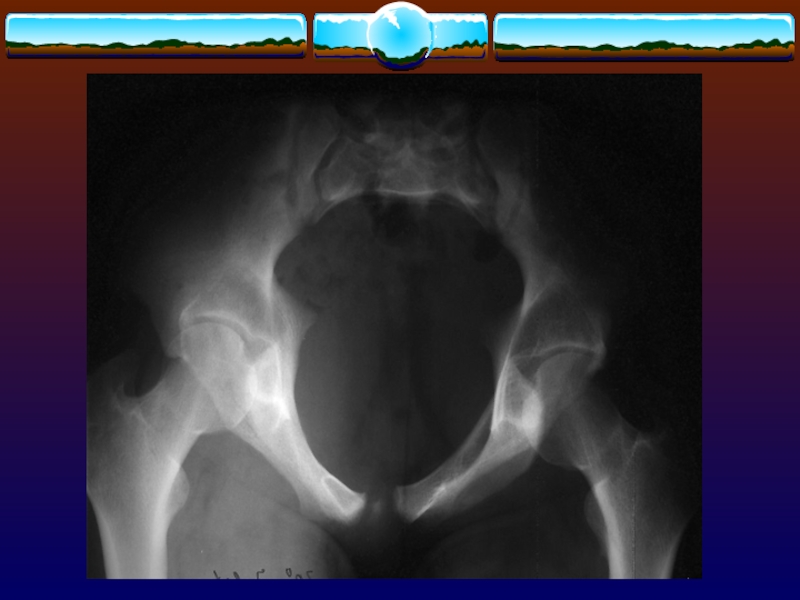

Слайд 74Перелом типа 61А

Перелом типа 61А

Слайд 75Перелом типа 61А1

Перелом типа 61А1

Слайд 77Перелом типа 61А2

Перелом типа 61А2

Слайд 79Перелом типа 61А3

Перелом типа 61А3

Слайд 81Перелом типа 61В

Перелом типа 61В

Слайд 82Перелом типа 61В3

Перелом типа 61В3

Слайд 84Перелом типа 61С

Перелом типа 61С

Слайд 85Перелом типа 61С3

Перелом типа 61С3